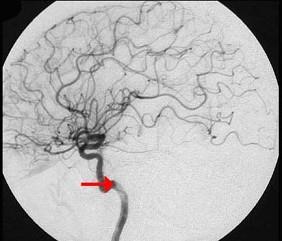

问题 如图箭头所示为大脑哪根动脉()

选项 A.颈内动脉 B.颈总动脉 C.大脑中动脉 D.基底动脉 E.大脑后动脉

答案 A